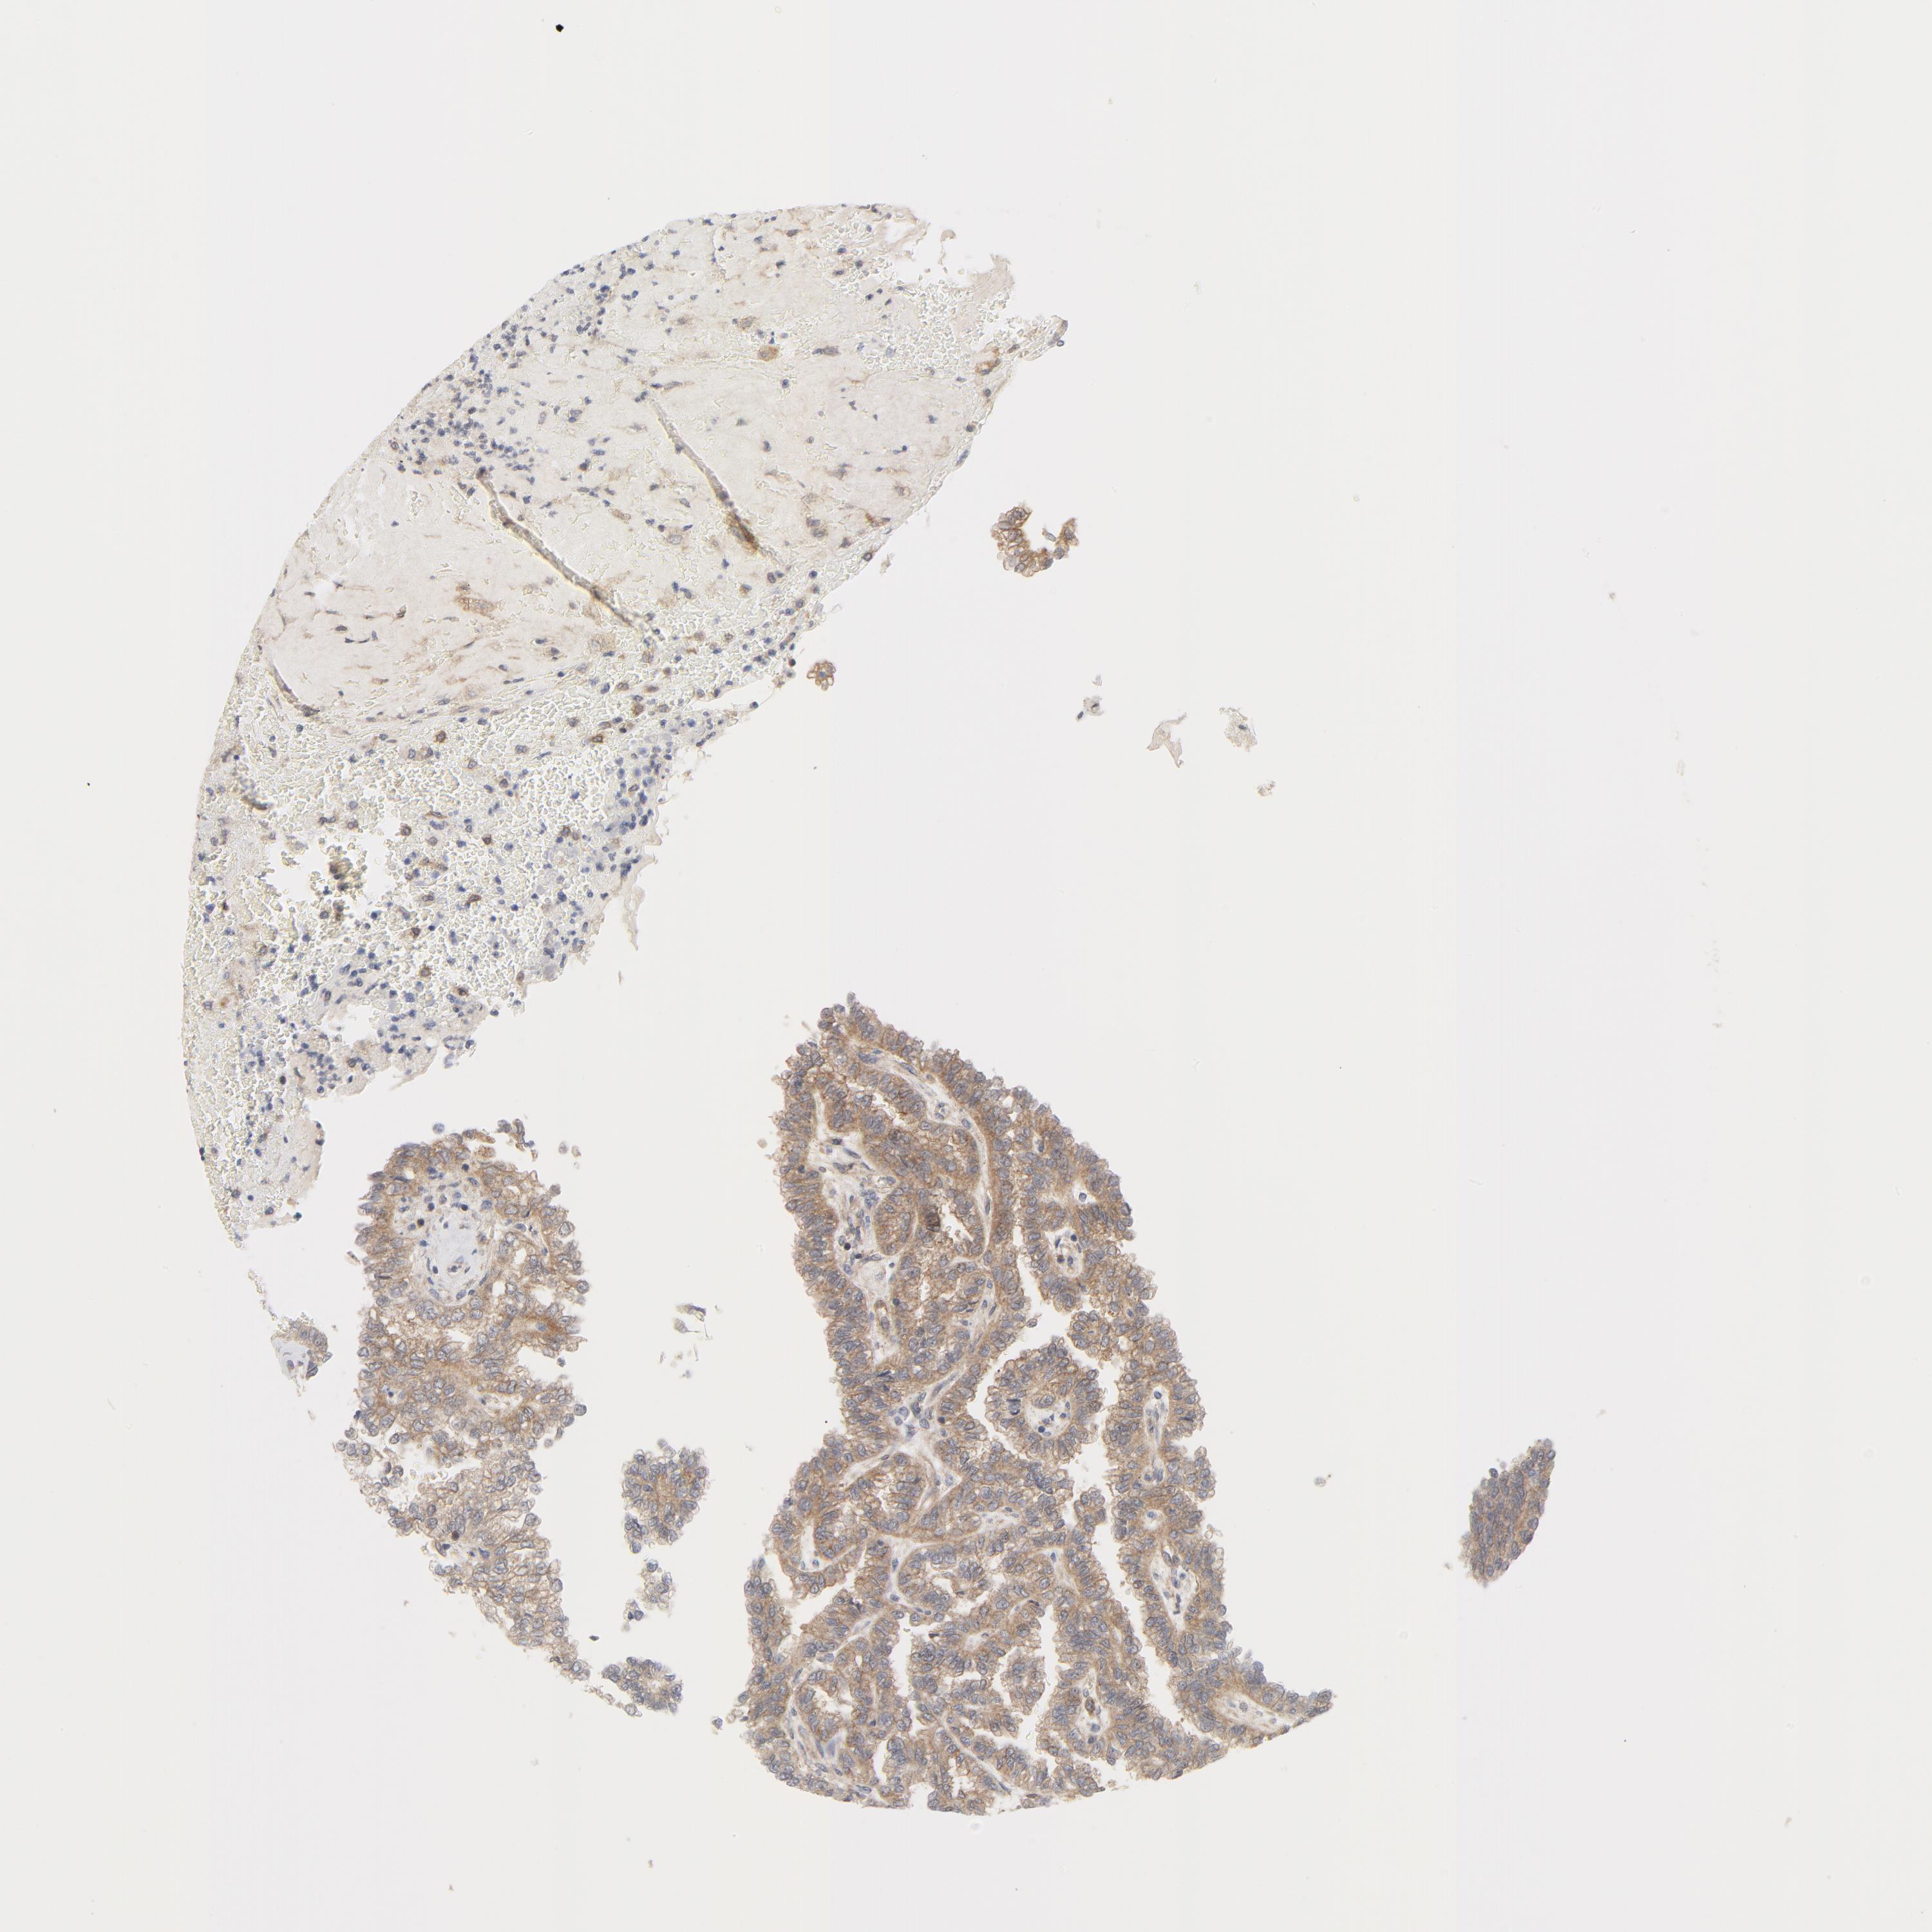

KIDNEY RENAL CLEAR CELL CARCINOMA (VALIDATION) - Interactive survival scatter ploti

The Survival Scatter plot shows the clinical status (i.e. dead or alive) for all individuals in the patient cohort, based on the same data that underlies the corresponding Kaplan-Meier plots. Patients that are alive at last time for follow-up are shown in blue and patients who have died during the study are shown in red.

The x-axis shows the expression levels (FPKM) of the investigated gene in the tumor tissue at the time of diagnosis. The y-axis shows the follow-up time after diagnosis (years). Both axes are complimented with kernel density curves demonstrating the data density over the axes. The top density plot shows the expression levels (FPKM) distribution among dead (red) and alive patients (blue). The right density plot shows the data density of the survived years of dead patients with high and low expression levels respectively, stratified using the cutoff indicated by the vertical dashed line through the Survival Scatter plot. This cutoff is automatically defined based on the FPKM cutoff that minimizes the p-score. The cutoff can be changed by dragging the vertical line or by entering a cutoff value in the square labeled "Current cut-off".

Under the Survival Scatter plot the p-score landscape (black curve; left axis) is shown together with dead median separation (red curve; right axis). Dead median separation is the difference in median mRNA expression between patients who have died with high and low expression, respectively. It is calculated as follows: median FPKM expression of dead patients with high expression - median FPKM expression of dead patients with low expression. This is intended to aid the user in visually exploring custom cutoffs and the associated p-scores and dead median separation.

Individual patient data is displayed and can be filtered by clicking on one or more of the category buttons on the top of the page. Categories describing expression level and patient information include: high, low, alive, dead, female, male and tumor stages. The scale of the x-axis can be toggled between linear and log-scale by clicking on the "x log" button. Mouse-over function shows TCGA ID, patient information and mRNA expression (FPKM) for each patient.

& Survival analysisi

Kaplan-Meier plots summarize results from analysis of correlation between mRNA expression level and patient survival. Patients were divided based on level of expression into one of the two groups "low" (under cut off) or "high" (over cut off). X-axis shows time for survival (years) and y-axis shows the probability of survival, where 1.0 corresponds to 100 percent.

MAP2K7 is not prognostic in Kidney Renal Clear Cell Carcinoma (validation)

Best expression cut offi

Based on the FPKM value of each gene, patients were classified into two groups and association between prognosis (survival) and gene expression (FPKM) was examined. The best expression cut-off refers the FPKM value that yields maximal difference with regard to survival between the two groups at the lowest log-rank P-value. Best expression cut-off was selected based on survival analysis .

When clicking on this number, the vertical dashed line indicating cut-off, the interactive survival plot, and the Kaplan-Meier curve will be adjusted to show results based on the best expression cut-off.

: 15.71

TCGA RNA samplesi

RNA-seq data is reported as average FPKM (number Fragments Per Kilobase of exon per Million reads), generated by the The Cancer Genome Atlas (TCGA) .

Normal distribution across the dataset is visualized with box plots, shown as median and 25th and 75th percentiles. Points are displayed as outliers if they are above or below 1.5 times the interquartile range. FPKM values of the individual samples are presented next to the box plot.

Average pTPM 19.9

Number of samples 100